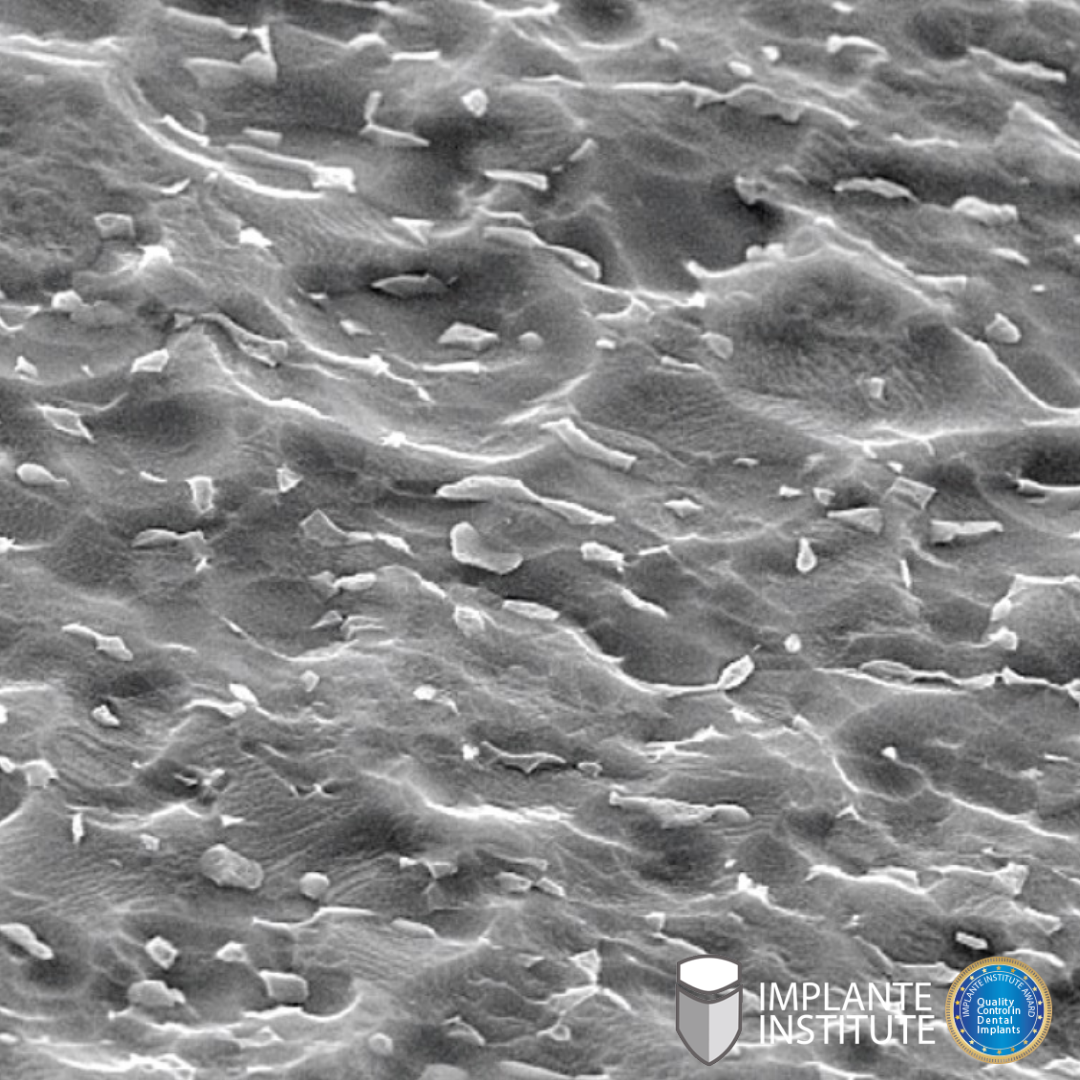

Fique seguro. E sim, isso branco na imagem é alumínio!

Stay safe. And yes, that white in the picture is aluminum!